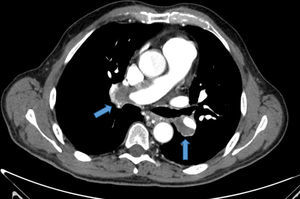

Presentamos el caso de un varón de 58 años diagnosticado de hipertensión pulmonar tromboembólica crónica (HPTEC), sometido a cirugía de endarterectomía pulmonar (EAP) bilateral, con excelente resultado. El paciente, con antecedente de hipertensión arterial bien controlada, con tratamiento con antagonistas de los receptores de la angiotensina II, consultó por astenia y disnea de varios meses de evolución, que había ido en aumento hasta hacerse de mínimos esfuerzos, presentando 7 días antes de su ingreso un episodio de mareo intenso. Su estado general era bueno, con adecuada perfusión de la piel y las mucosas. En la exploración física, la tensión arterial era de 120/64mmHg, la frecuencia cardiaca de 65lpm y la respiratoria de 14rpm. Presentaba ventilación pulmonar conservada y un soplo sistólico en foco tricuspídeo, grado II/IV, sin irradiación y con segundo tono normal en la auscultación cardiaca. La radiografía de tórax mostró una silueta cardiomediastínica dentro de la normalidad, y sin datos de enfermedad pleuropulmonar. En el electrocardiograma se advertía un ritmo sinusal con extrasístoles auriculares aisladas. La saturación arterial de oxígeno (SpaO2) era del 94,2%, con una presión parcial de O2 de 68,0mmHg y una presión parcial de CO2 de 34,0mmHg. La determinación del dímero D resultó normal. La angio-tomografía computarizada (angio-TC) torácica evidenció defectos de repleción en ambas arterias pulmonares principales, compatible con trombo crónico (fig. 1). La eco-Doppler de miembros inferiores no mostró datos de trombosis venosa profunda. Se practicó un ecocardiograma Doppler que mostró un ventrículo izquierdo con diámetros normales con función global conservada, así como una insuficiencia tricuspídea (IT) moderada y una presión sistólica pulmonar estimada (PSAPe) de 125mmHg, con moderada dilatación de cavidades derechas. El paciente fue diagnosticado de hipertensión pulmonar (HP) secundaria a embolia pulmonar (EP) crónica y tratada con anticoagulación. En el seguimiento a los 3 meses, el paciente mantenía disnea clase III de la World Health Organization (WHO), y en la ecocardiografía Doppler cavidades derechas moderadamente dilatadas con una IT leve y una PSAPe de 75mmHg. El estudio de hipercoagulabilidad resultó normal. El paciente fue sometido al protocolo diagnóstico de HPTEC: se practicó una gammagrafía de perfusión pulmonar que mostró múltiples defectos de perfusión intrapulmonares en segmentos superior e inferior de ambos campos pulmonares, hallazgos compatibles con alta probabilidad de EP; la espirometría mostró una limitación ventilatoria restrictiva de grado moderado; la prueba de marcha de los 6min (PM6M), realizada en aire ambiente, mostró una distancia total recorrida de 400m, SpaO2 basal del 94% y SpaO2 final del 88% (puntuación 7 en la escala Borg); el cateterismo cardiaco derecho confirmó una presión media arterial pulmonar (PmAP) de 47mmHg; y finalmente, se realizó una arteriografía digital pulmonar que mostró defectos de vascularización centrales en ambos pulmones, y una coronariografía que descartó enfermedad arterial coronaria. Previa implantación de un filtro de Greenfield en la vena cava inferior, se practicó al paciente una EAP bilateral mediante esternotomía media, con apoyo de circulación extracorpórea y periodos de parada circulatoria intermitente en hipotermia profunda (fig. 2). No se produjeron complicaciones posoperatorias. En el control a los 90 días, tras la cirugía, el paciente se encontraba en clase funcional I de la WHO con una SpaO2 del 99%, respirando aire ambiente. La nueva PM6M mostró una distancia total recorrida de 470m y una SpaO2 basal del 99% con una SpaO2 final del 94% (puntuación 1 en la escala de Borg). El estudio de la función pulmonar resultó normal y el ecocardiograma Doppler mostró una PSAPe de 35mmHg, con cavidades derechas de tamaño normal. En la angio-TC torácica no se identificaron defectos de repleción intravasculares (fig. 3). Todos los pacientes con HPTEC deben recibir anticoagulación indefinida con el fin de prevenir la trombosis in situ y el tromboembolismo recurrente1. La cirugía de EAP es el tratamiento de elección de la HPTEC, en los casos en que se estime que esta intervención permitirá la extracción de una cantidad significativa de material fibrotrombótico de las arterias pulmonares. La EAP es el único tratamiento que puede lograr la curación de la HPTEC, y es apropiada para más del 60% de los pacientes. La EAP consiste en la extracción quirúrgica del material trombótico intravascular organizado, la capa íntima engrosada, a la cual aquel está firmemente adherido, y parte de la capa muscular. La endarterectomía debe ser bilateral y completa, es decir, extirpando el material fibrotrombótico más periférico. Para ello se requiere esternotomía media, circulación extracorpórea y pausas de parada circulatoria completa que permitan visualizar adecuadamente el árbol vascular. Para evitar el posible daño cerebral durante la parada circulatoria, estas se limitan a una duración menor de 20min por lado, y se realizan en hipotermia profunda de entre 18-20°C. La intervención proporciona unos excelentes resultados, con un porcentaje de curación de la HP (valor de PmAP posoperatorio<25mmHg) cercano al 50%, mejoría de la hemodinámica y de la tolerancia al esfuerzo francas, y buena supervivencia a largo plazo2. La EAP no está exenta de complicaciones y requiere de experiencia, tanto del procedimiento quirúrgico como del manejo perioperatorio. La mortalidad en el periodo posoperatorio en los centros con mayor experiencia es actualmente del 4-5%. En un registro en el que se incluyeron 386 pacientes de 26 centros expertos europeos y uno canadiense, la mortalidad en el posoperatorio inmediato fue del 4,7%. Las complicaciones posoperatorias más frecuentes son el edema de reperfusión y la HP persistente tras la cirugía. La decisión debe ser individualizada para cada paciente, puesto que en el éxito de la cirugía interviene la relación que existe entre las lesiones trombóticas accesibles quirúrgicamente y el estado hemodinámico, la función del ventrículo derecho, la edad del paciente y las comorbilidades, entre otros factores. La angioplastia con balón de las arterias pulmonares es una técnica que se ha postulado en los últimos años, y que se podría tener en cuenta para pacientes que se consideran inoperables debido a enfermedad predominantemente distal o a enfermedades asociadas o en aquellos pacientes con HP persistente o recurrente después de la EAP.